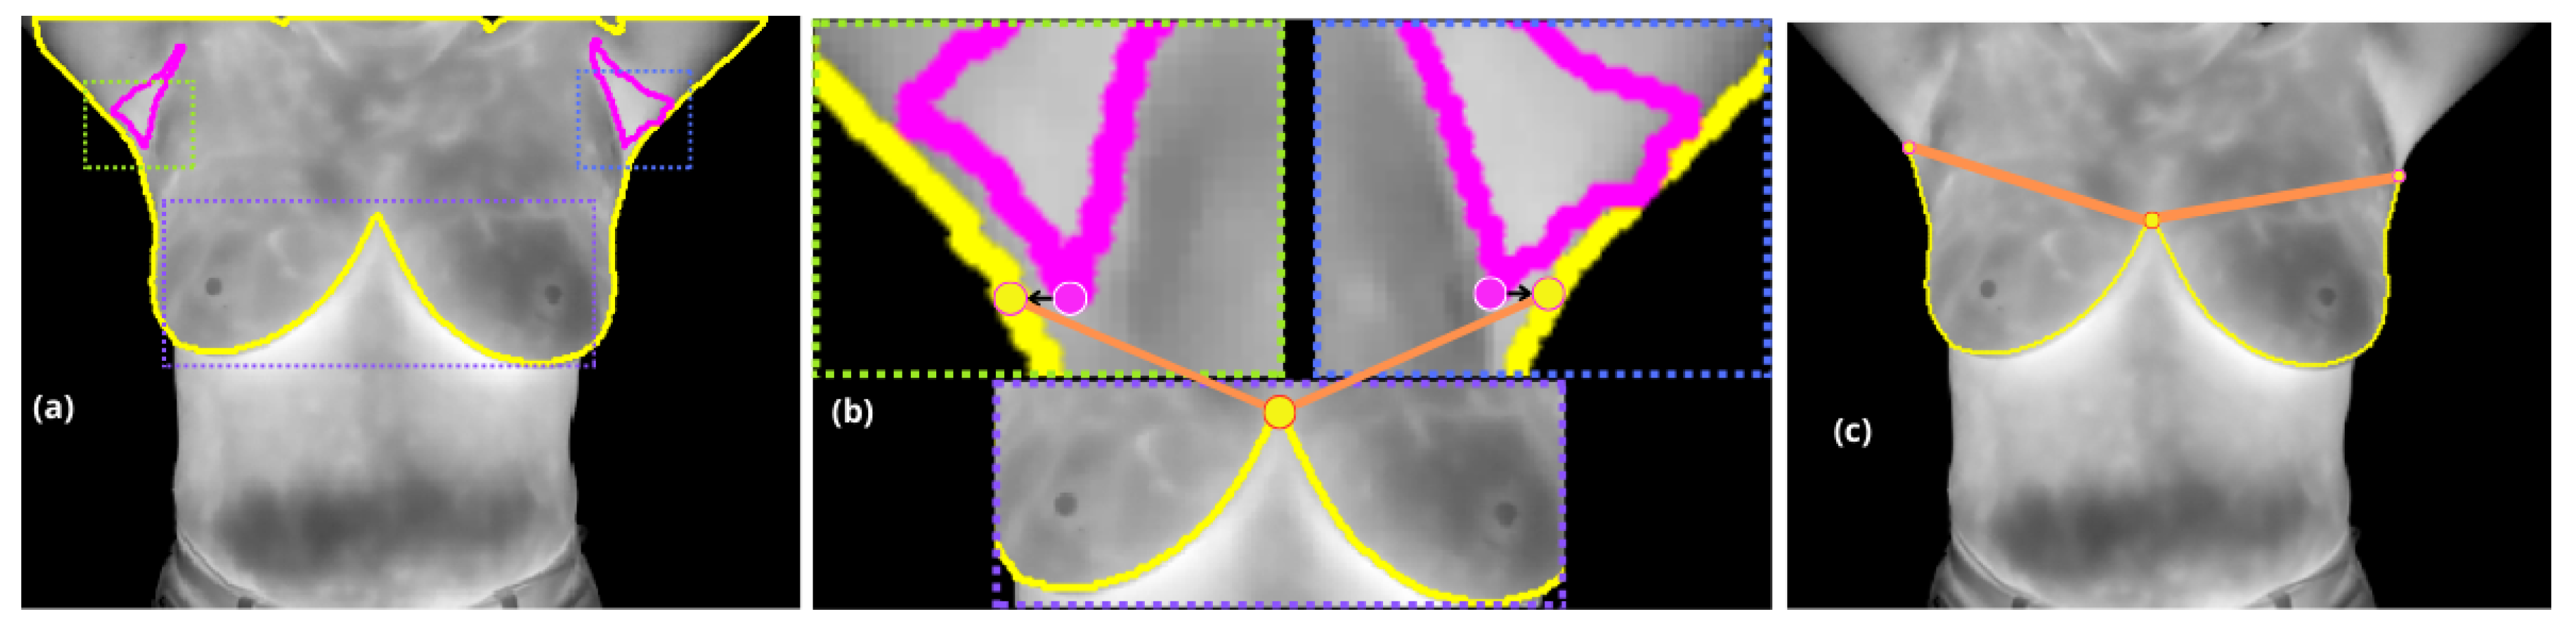

In the second stage, with the extracted contour from α m a s k ( b r ) , where boundary pixels are identified based on their neighborhood connectivity, the inter-inframammary inflection point is detected through further analysis.

Pixels with incomplete connectivity within a 3 × 3 neighborhood are marked as boundary points and organized into an ordered list of coordinates ( x i , y i ) . This contour serves as the basis for further analysis, including curvature estimation and inflection point detection.

A localized approach is employed, analyzing curvature variations within a range of ± Δ d around each point on the contour. Each curvature point is evaluated to detect significant changes, but specifically, the inter-inframammary inflection point, denoted p 1 , is defined as the location where the curvature reaches a local maximum, marking a significant directional change along the contour [22].

Finally, the axillary regions ( α m a s k ( a r ) ) are treated as distinct objects (i.e. a connected component). The lowest pixel attribute within these regions is projected horizontally along the x-axis (image columns) to the nearest lateral edge of α m a s k ( b r ) . Points p 1 and p 2 are then utilized to draw a straight line, which serves to define the supramammary boundary, resulting in a complete segmentation of the breasts, see Figure 3.

Figure 3. (a) Displays the segmentation contours α m a s k ( b r ) in yellow and α m a s k ( a r ) in magenta. The different dashed rectangles represent the regions to be analyzed in the cropped images in (b): the right axilla in green, the left axilla in blue, and the inframammary bifurcation in purple. (b) Shows the both projections from the lower armpit pixels, right and left (marked with a magenta circle with a white border) to the nearest pixel on the yellow contour (marked with yellow circle with a magenta border), and the upper inflection point of the inframammary bifurcation (marked by a yellow circle with an orange border). (c) These points define the supramammary borders, marked in orange.